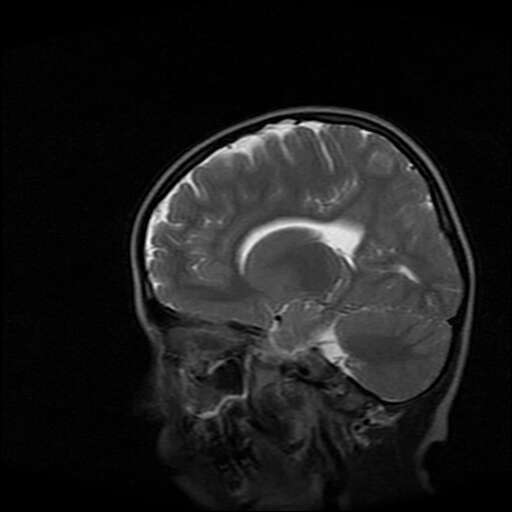

女,7岁,三岁才说话、走路。现智力尚可,走路不稳。临床怀疑大脑发育不全。

脑折质变薄,双侧侧脑室稍扩张,支持考虑脑折质发育不良

考虑胼胝体发育不全,髓鞘形成不良。

支持考虑胼胝体发育不全,髓鞘形成不良。

侧脑室周围白质数量减少,侧脑室不对称性扩大,左侧侧脑室后角呈方形改变,脑沟加深,结合临床考虑脑室周围白质软化症(pvl)。期待结果!